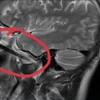

Ngày 7/4, thông tin từ Bệnh viện II Lâm Đồng cho biết đã mổ thành công, lấy được con dao bầu dài 30cm ra khỏi hốc mắt của Nguyễn Lý H., 15 tuổi, trú tại tại xã Tân Lâm, huyện Di Linh (Lâm Đồng).

Ngay sau khi nhập viện, bệnh nhân được sơ cứu và chuyển lên phòng mổ cấp cứu. Sau khoảng 30 phút, ca mổ thành công.

Các y, bác sỹ đã lấy con dao ra khỏi hốc mắt của thiếu niên này. Rất may, mắt bệnh nhân Nguyễn Lý H. chỉ bị tổn thương nhẹ. Sau khi ca mổ thành công, bệnh nhân H. ở lại Bệnh viện II Lâm Đồng tiếp tục theo dõi, điều trị.